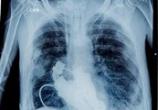

Амилоидоз Льюиса все больше прогрессировал, и врачи опасались, что он вскоре умрет, если не будут предприняты необходимые меры. По словам... →